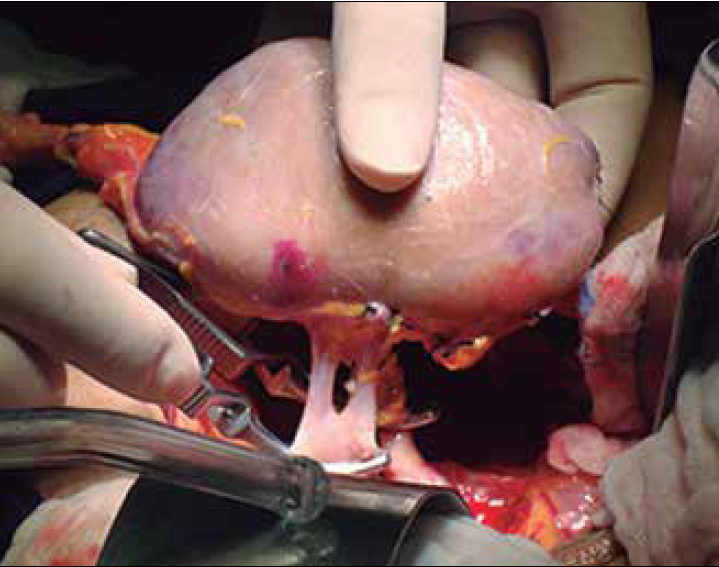

El 06 de mayo de 2014 se realizó el trasplante cardiaco ortotópico con técnica bicaval y 18 horas, después se efectuó trasplante renal derecho de un mismo donador cadavérico.

Posteriormente, a las 18 h del trasplante cardiaco, se decidió realizar el trasplante renal. El paciente ingresa a la sala de trasplante en VMC con monitoreo invasivo; por lo que respecta al manejo anestésico, se continua con fentanilo, midazolam y se cambia el relajante muscular por cisatracurio. Ya que el paciente donador para trasplante de corazón y riñón era cadavérico, el tiempo de isquemia fría total fue de 23 h, con un tiempo en la máquina de perfusión pulsátil renal de aproximadamente 18 h.